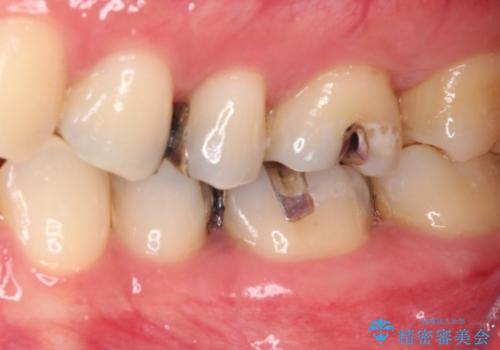

銀歯をセラミックにしたい セラミックインレー修復

- 銀歯をセラミックにしたいとのことで来院された患者様です。

まず麻酔をして銀歯を外し、むし歯を除去し、形を整えて型取りします。

そして次の来院時、セラミックインレーを装着し、噛み合わせなどの調整を行います。

それを左右に分けて行いました。

インレーを装着するときは、唾液や血液による接着力の低下を避けるためにラバーダム防湿を行いました。